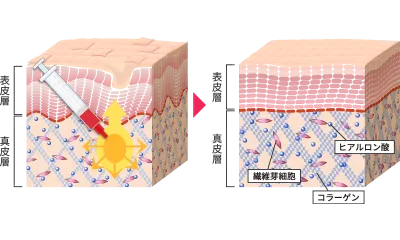

PRP注射とは

による

肌細胞の再生

当院のPRPは独自の遠心分離法により通常の10倍以上の濃度の成長因子を抽出しております。また、注入部位やお求めの効果、肌質などにより、PRP治療に精通した医師が、お客様ごとに医療用成長因子(FGF)の最適な濃度を6種類の中から判断して、配合しております。

PRP注射が効果的な理由

PRP注射には6種類の配合が存在します。体質やご年齢、注入部位によって、最適な配合を使い分けることにより、どなたでも確実な肌再生効果が得られます。